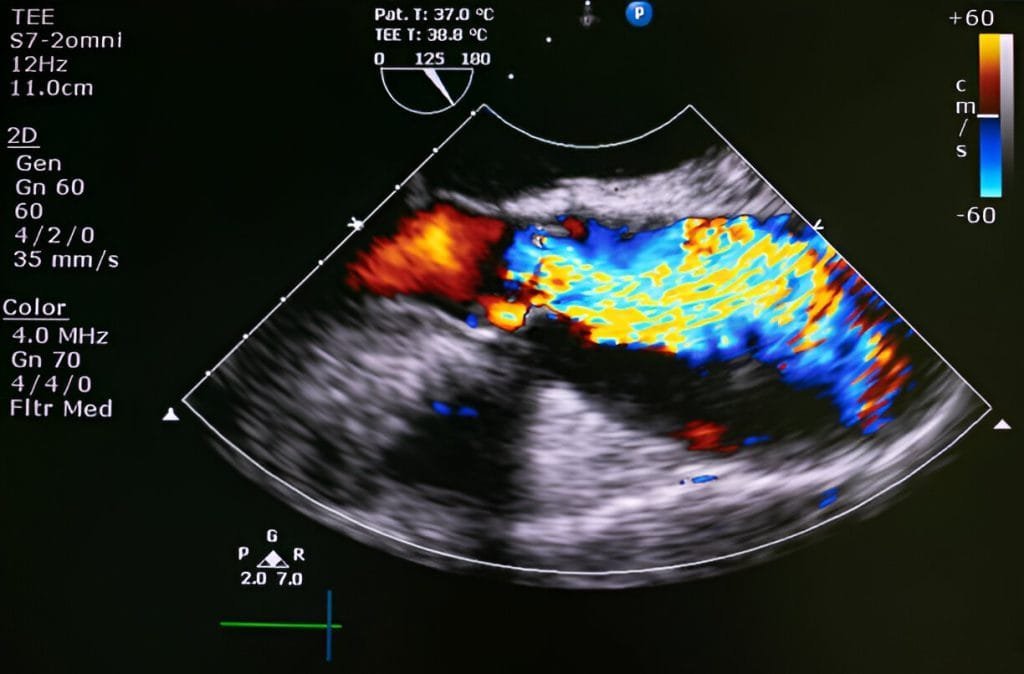

Echocardiography is a non-invasive imaging technique that uses sound waves to create detailed images of the heart’s structures, including its chambers, valves, and blood flow patterns.

During an echocardiogram, a transducer (a small handheld device) is placed on the chest or sometimes inside the oesophagus to emit high-frequency sound waves. These sound waves bounce off the heart’s structures and are captured by the transducer to create real-time images on a monitor. Echocardiography can be performed from different angles to obtain comprehensive views of the heart.

The technique provides critical information about the heart’s size, shape, function, and blood flow dynamics. It is used to diagnose and assess conditions such as heart valve abnormalities (stenosis, regurgitation), cardiomyopathies (enlarged or weakened heart muscle), congenital heart defects, pericardial effusions (fluid around the heart), and more.